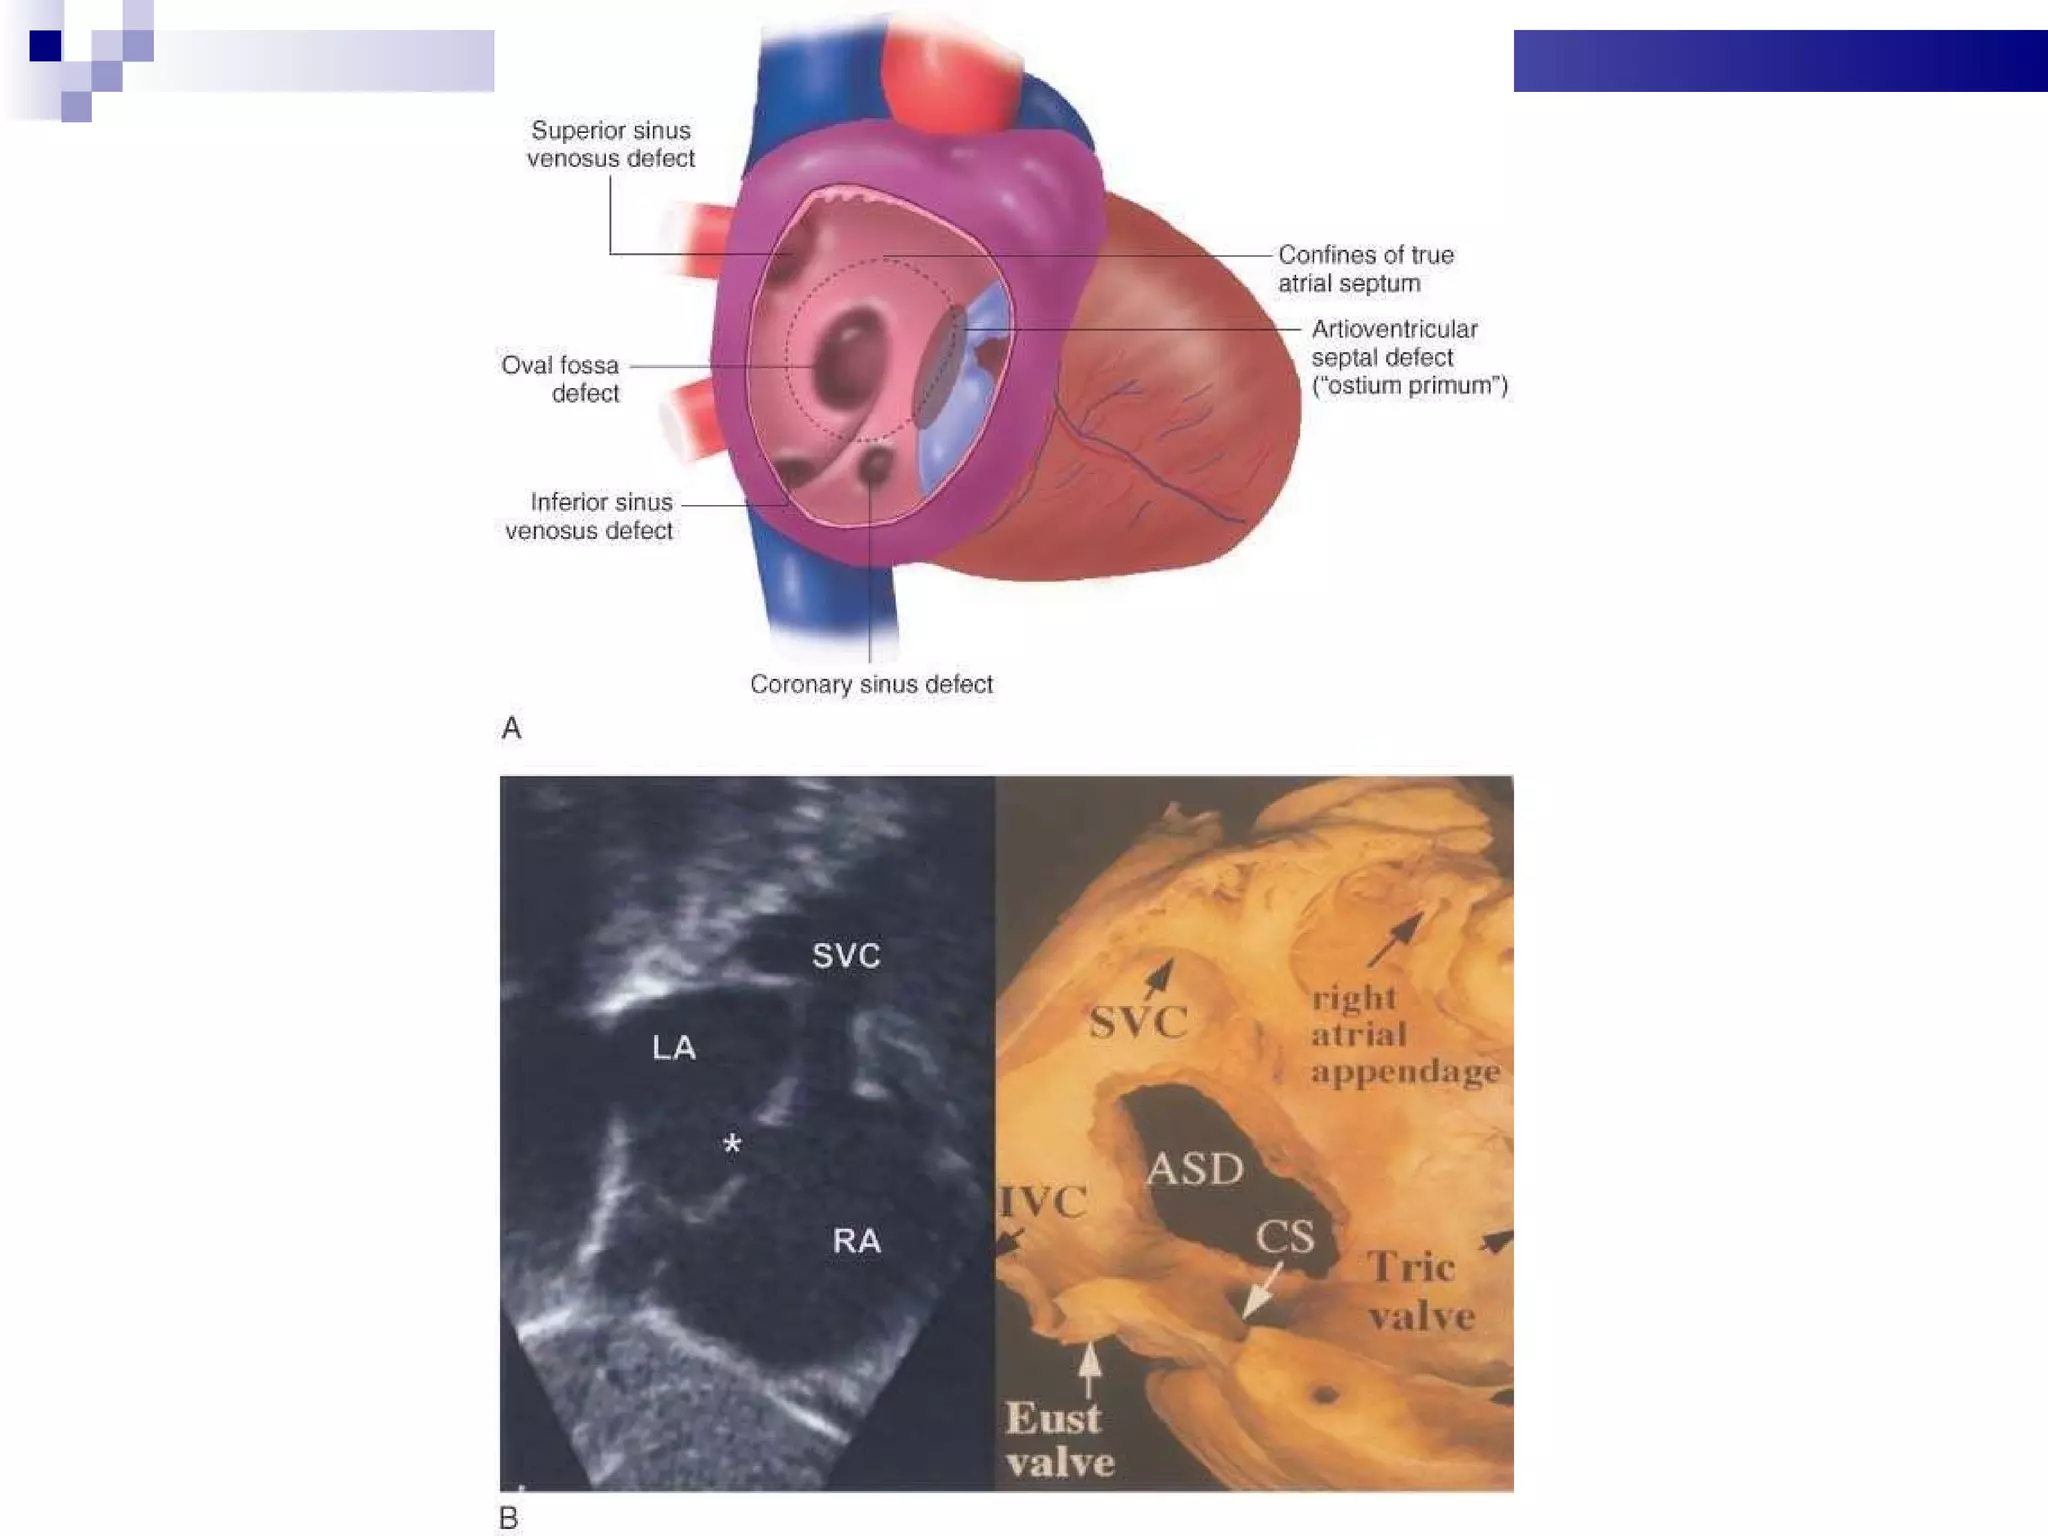

Morphology 4 Types of ASD:  * ostium primum * ostium secundum * sinus venosus * coronary sinus defects  ↑ Left to right shunt:  * left ventricular compliance↓  * left atrial pressure  ↑

Intervention Device closure  * For secundum ASD with stretched diameter < 36 mm + adequate rims  * Exception: 1) Anomalous pulmonary venous connection 2) Proximity to the AV valves / coronary sinus / systemic  venous drainage Surgery * For sinus venosus or ostium primum defects or with secundum defects with unsuitable anatomy  * primary suture closure or using a pericardial or synthetic patch

Percutaneous ASD closure Percutaneous closure of an ASD is indicated for the closure of secundum ASDs with a sufficient rim of tissue around the septal defect so that the closure device does not impinge upon the  SVC ,  IVC , or the  tricuspid  or  mitral  valves.  The  Amplatzer  Septal Occluder (ASO) is commonly used to close ASDs. The ASO consists of two self-expandable round discs connected to each other with a 4 mm waist, made up of 0.004–0.005´´ Nitinol wire mesh filled with Dacron fabric. Implantation of the device is relatively easy. The prevalence of residual defect is low.  Percutaneous closure is the method of choice in most centres.

Morphology 4 Typesof ASD: * ostium primum * ostium secundum * sinus venosus * coronary sinus defects ↑ Left to right shunt: * left ventricular compliance↓ * left atrial pressure ↑

Percutaneous ASD closurePercutaneous closure of an ASD is indicated for the closure of secundum ASDs with a sufficient rim of tissue around the septal defect so that the closure device does not impinge upon the SVC , IVC , or the tricuspid or mitral valves. The Amplatzer Septal Occluder (ASO) is commonly used to close ASDs. The ASO consists of two self-expandable round discs connected to each other with a 4 mm waist, made up of 0.004–0.005´´ Nitinol wire mesh filled with Dacron fabric. Implantation of the device is relatively easy. The prevalence of residual defect is low. Percutaneous closure is the method of choice in most centres.